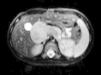

Bioquímica sanguínea: bilirrubina total 4,32 mg/dl (rango normal: 0,3-1,30), bilirrubina directa 3,42 mg/dl (rango normal 0,0-0,30), GOT 103 U/l (rango normal: 28-64), GPT 178 U/l (rango normal: 15-48), fosfatasa alcalina 2.402 U/l (rango normal: 122-290), GGT 497 U/l (rango normal: 8-30), LDH 540 U/l (rango normal: 120-460). Enolasa neuronal específica: 31 μg/l (rango normal: 0-12,5). Alfafetoproteína normal. Hemograma normal. La serología para virus hepatotropos fue negativa. En las pruebas de imagen (ecografía, tomografía computarizada [TC] y resonancia magnética) se visualizaba una masa sólida de contornos bien definidos de 6 x 5 x 4 cm que crecía en torno a los vasos mesentéricos, tronco celíaco y se prolongaba hacia el hilio hepático comprimiendo la vía biliar y desplazando la cabeza del páncreas. La lesión se situaba en un plano más bajo que la glándula suprarrenal y no parecía relacionarse con ella (fig. 1). Gammagrafía con MIBG con 123 I: se apreciaba marcado depósito del radiotrazador en la zona infrahepática que descendía hasta el flanco derecho continuando de forma lineal en región epigástrica y mesogástrica. Se extendía hacia el hipocondrio y flanco izquierdos, dibujando una masa de forma ovalada en el lado derecho y otra de menor tamaño redondeada en el lado izquierdo, ambas conectadas en su parte interna con gran necrosis en el interior de toda la masa descrita (fig. 2). Catecolaminas en orina: ácido vanilmandélico: 10,65 μg/mg creatinina (rango normal: 2-10), ácido homovanílico 6,63 μg/mg creatinina (rango normal: 3-20).

Figura 1. Resonancia magnética abdominal del tumor.